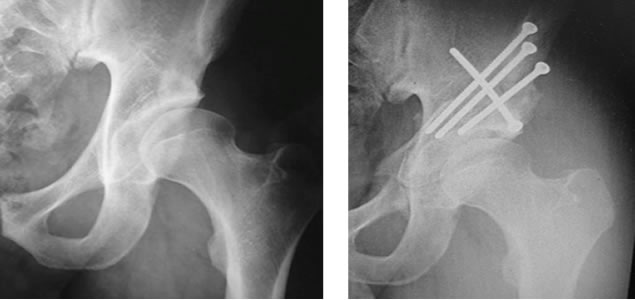

En 1988, Reinhold Ganz describió una técnica quirúrgica para el tratamiento de la displasia de cadera. Actualmente existen diversas técnicas o modificaciones de la técnica original, que consisten en realizar cortes alrededor de la articulación (en el fémur o pelvis) para orientar correctamente los componentes articulares y distribuir las cargas sobre el cartílago, mejorando la función.

Existe una alteración en la orientación y la cobertura articular, que predispone a un mal funcionamiento de la cadera, con un consecuente daño. La evolución natural consiste en daño articular, lesión de labrum y cartílago, y su consecuente artrosis precoz.

El tratamiento quirúrgico tiene una indicación precisa, principalmente en paciente jóvenes sin artrosis o estadios iniciales, con buenos resultados de acuerdo al daño al momento del tratamiento.